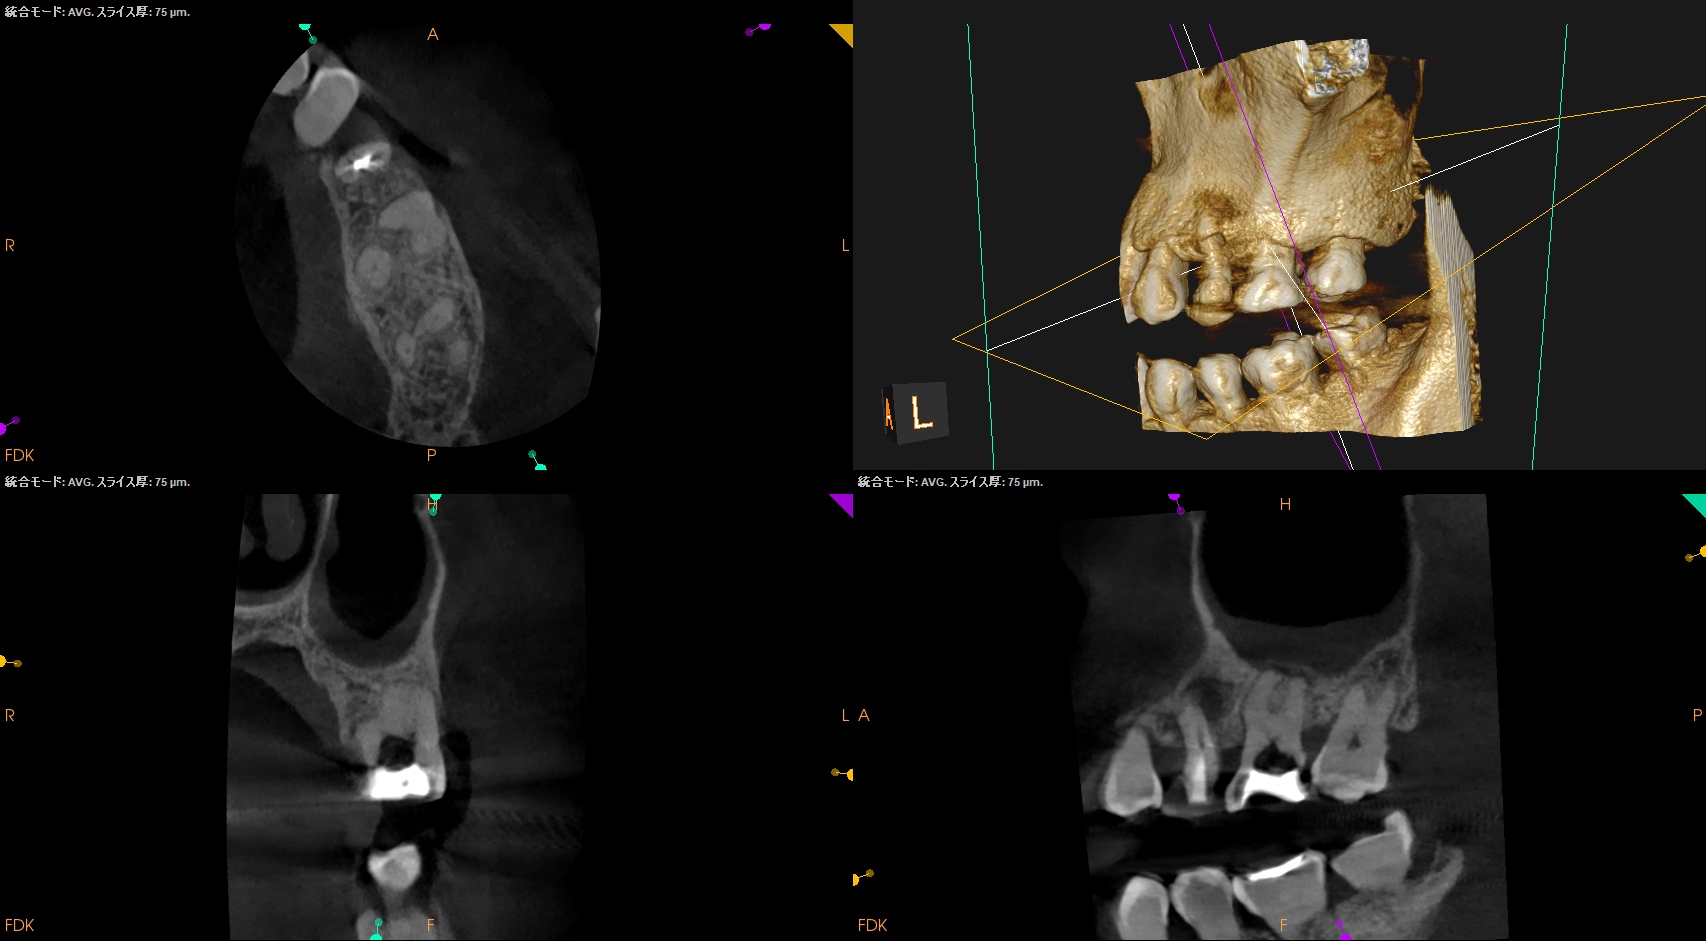

CBCTも撮影した。

これはマストの医療行為である、と私からは告げておこう。

#14

MB

MB2

DB

P

B

さておき、#13にも病変があるのがわかるので#13も分析した。

が、いずれにしてもこの治療での最大のポイントになるのはMB2がどこにあるか?である。

MB2の根尖部にはCBCTで根尖病変があるからだ。